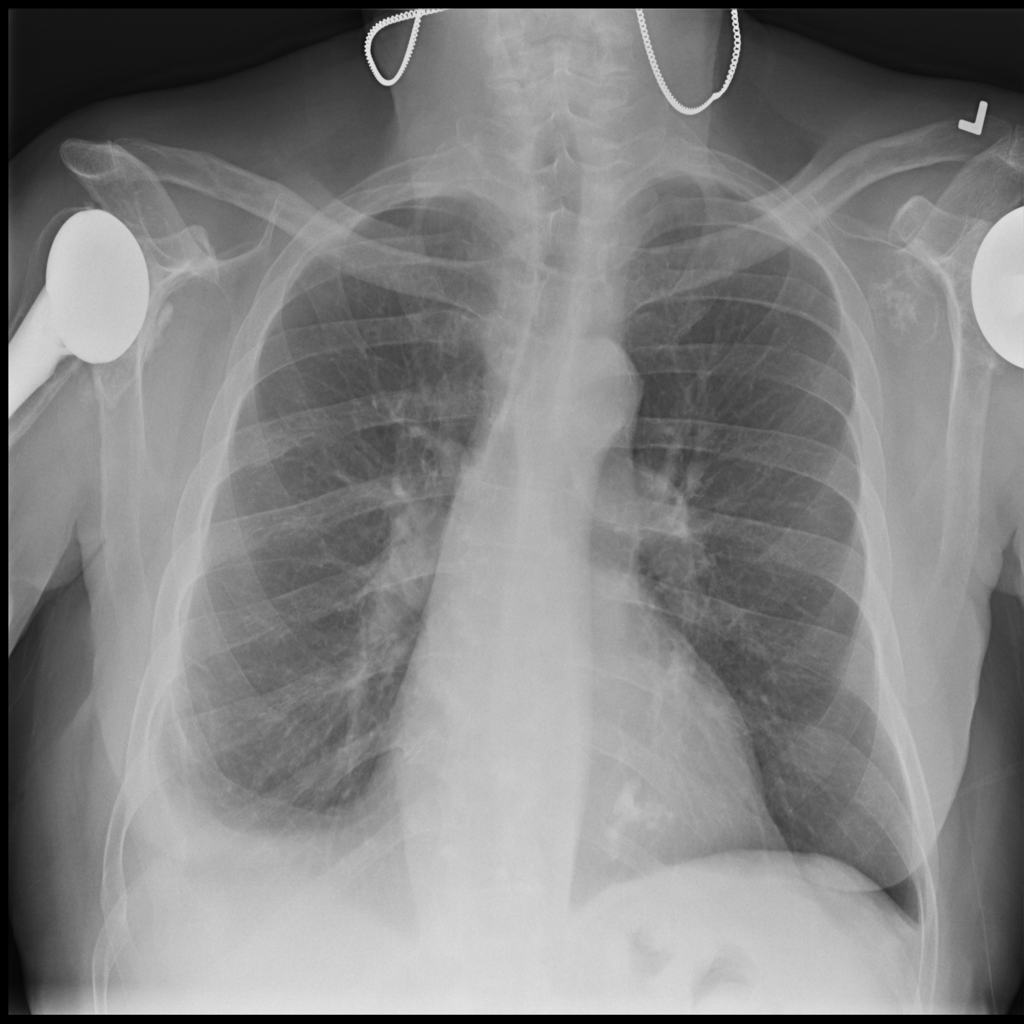

PAT-4639 · IMG-021Effusion

PAT-4639 · IMG-021

PA